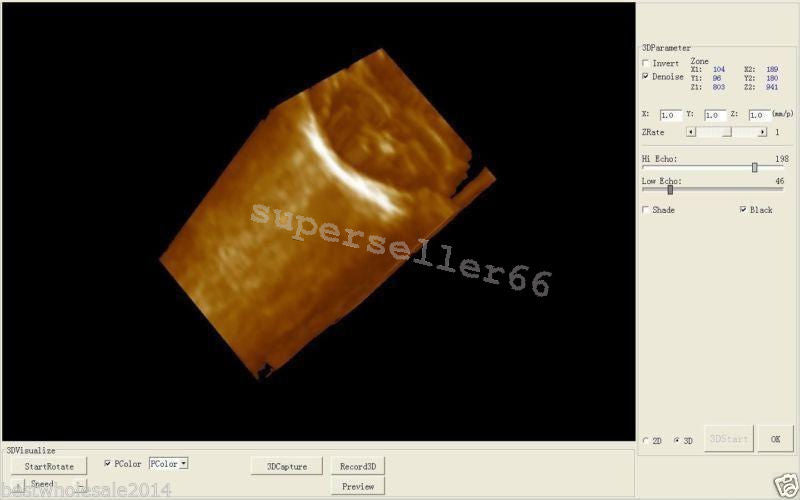

High-Resolution Display for Clear Imaging

The Ultrasound Scanner features a 10.1'' LCD screen that provides high-resolution images, ensuring that healthcare professionals can make accurate diagnoses. However, the clarity of ultrasound imaging is vital, because it directly impacts patient care. The intuitive interface makes it easy for users to navigate through various options, so they can focus on delivering quality healthcare.